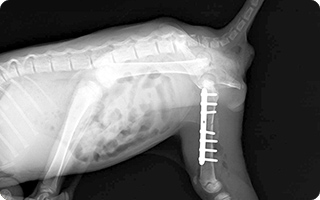

整形外科

関節の病気や骨折、靭帯や腱の損傷などを治療いたします。歩き方がおかしい時や足つきなどが気になる時にもご相談ください。

当院では整形外科に力を入れており、動物たちへできるだけストレスを与えない治療を心がけております。骨折などの症状で他院で治療を断られてしまった場合にもできるだけ診療を行います。まずはお気軽にご来院ください。